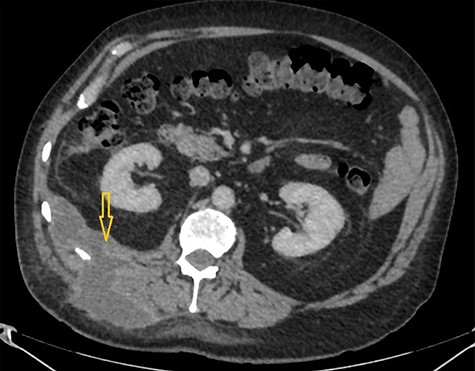

A CT scan abdomen was performed, which demonstrated a large retroperitoneal abscess behind the liver tracking through a small intramuscular opening onto the skin over the upper aspect of the back (Fig. 2).

Because of previously identified calcification in the mass lesion and history of laparoscopic cholecystectomy, a non-contrast CT scan abdomen was obtained to ascertain if spilled gallstones were responsible for the recurrent abscess formation (Fig. 3).

CT scan abdomen demonstrates a retroperitoneal abscess tracking through an intramuscular opening onto skin in the right paraspinal region.